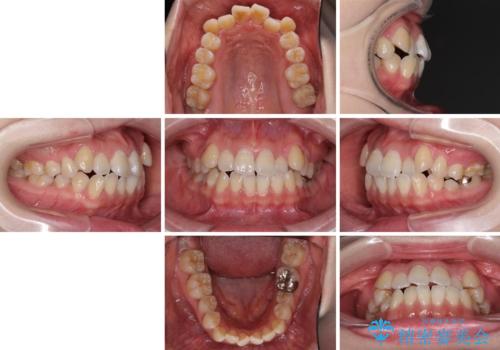

口元の突出感を改善 インビザラインによる非抜歯矯正

- 前歯がデコボコした上に口元が閉じにくいことを気にして来院された患者様です。

IPR(歯と歯の間を削る)と側方拡大では口の閉じにくさは改善できそうになく、一方で抜歯矯正を行うほどの突出感は認められませんでした。

親知らずを全て抜去し、歯列全体を後方に移動させることで口元の閉じにくさいを改善していくこととしました。

インビザラインでの歯列全体の後方移動は時間がかかりますが、しっかりと装着時間を守っていただいたので、スッキリとした口元に仕上げることができました。